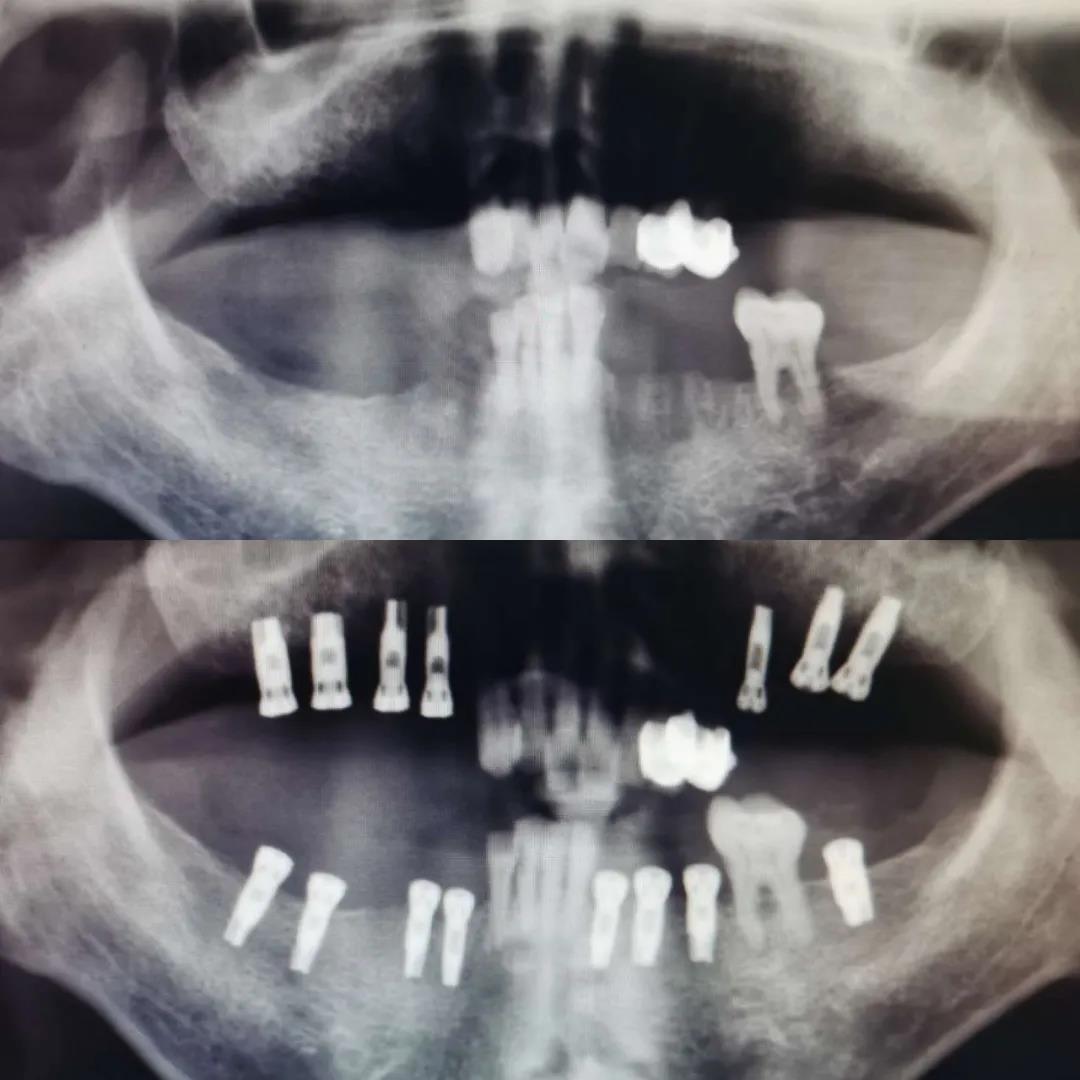

此次培訓(xùn)由美國(guó)哈佛大學(xué)牙學(xué)院博士張杰發(fā)起,江陰金泰克生物技術(shù)有限公司舉辦的。張杰博士和山西省口腔醫(yī)學(xué)會(huì)副會(huì)長(zhǎng)鄭強(qiáng)教授、金泰克旗下門診醫(yī)師張乙云共同為學(xué)員們呈現(xiàn)了一場(chǎng)精彩的口腔學(xué)術(shù)盛宴。種植技術(shù)示范現(xiàn)場(chǎng),鄭強(qiáng)教授和張乙云醫(yī)師一小時(shí)內(nèi)為患者種植牙15顆,現(xiàn)場(chǎng)觀摩學(xué)員無(wú)不對(duì)金泰克種植體系統(tǒng)先進(jìn)的設(shè)計(jì)原理和簡(jiǎn)易的操作方法表示稱贊。

學(xué)員現(xiàn)場(chǎng)觀摩鄭強(qiáng)教授手術(shù)示范,一小時(shí)內(nèi)完成15顆種植牙

手術(shù)過(guò)程時(shí)間持續(xù)一個(gè)小時(shí),患者缺失的主要為后牙部分,情況復(fù)雜,難度較高,術(shù)后無(wú)不適狀況,面部無(wú)腫痛。